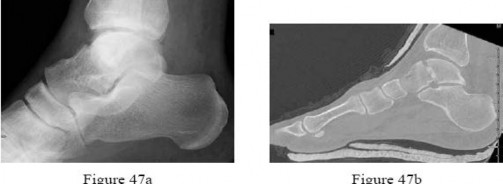

A 28-year-old male sustained a displaced talar neck fracture and underwent open reduction and internal fixation.

Six weeks postoperatively, a subchondral radiolucent band is seen in the talar dome on the AP mortise radiograph. What does this radiographic finding indicate?

Explanation

Hawkins sign is a subchondral radiolucent band seen in the talar dome 6 to 8 weeks after a talus fracture. It represents subchondral osteopenia secondary to disuse atrophy. Because bone resorption requires an active blood supply, the presence of a Hawkins sign is a highly reliable indicator that the talar body has intact vascularity and that avascular necrosis (AVN) is unlikely.